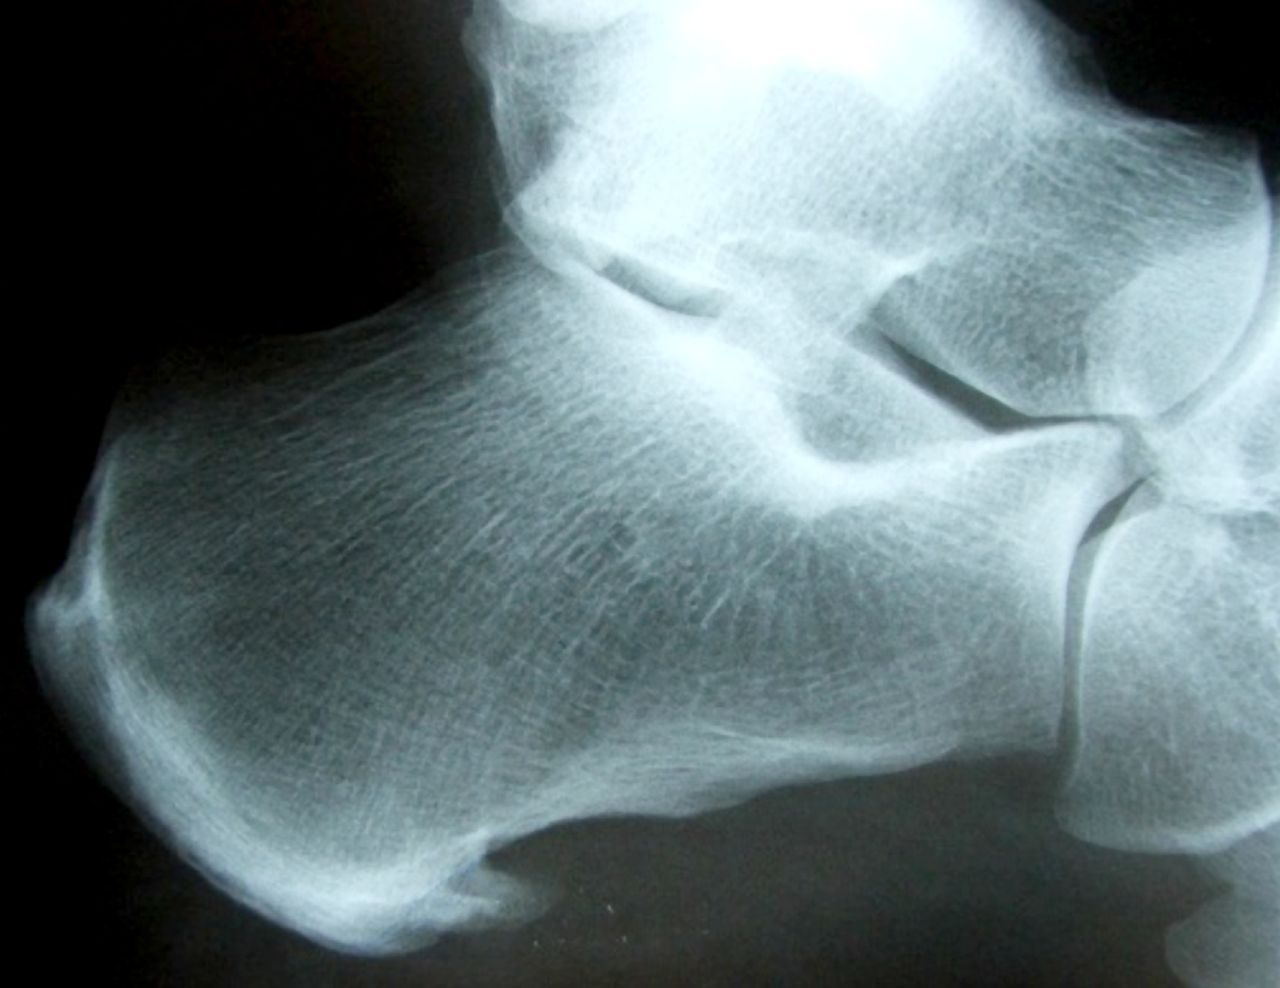

8.2 Diagnostic Imaging

Although diagnostic imaging can be used in the clinical management of plantar fasciitis, it does not commonly change management (Orchard, 2012). Many authors have established that, although the diagnostic imaging features of plantar fasciitis (such as heel spur on x ray (Figure 3) (Irving et al., 2006) thickened plantar fascia on ultrasound (Akfirat et al., 2003), and “hot” bone scan on calcaneus) are far more common in patients with heel pain, they can occur in asymptomatic individuals and be absent in cases of plantar fasciitis.

It is recognised that the pain is not simply due to a heel spur, although the exact cause of pain in plantar fasciitis (and other enthesopathies) remains uncertain (Orchard, 2012). Where the diagnosis is unclear from the standard clinical assessment, pain relief on walking after an ultrasound guided injection of local anaesthetic to the plantar fascia origin can help to confirm the diagnosis (Orchard, 2002).